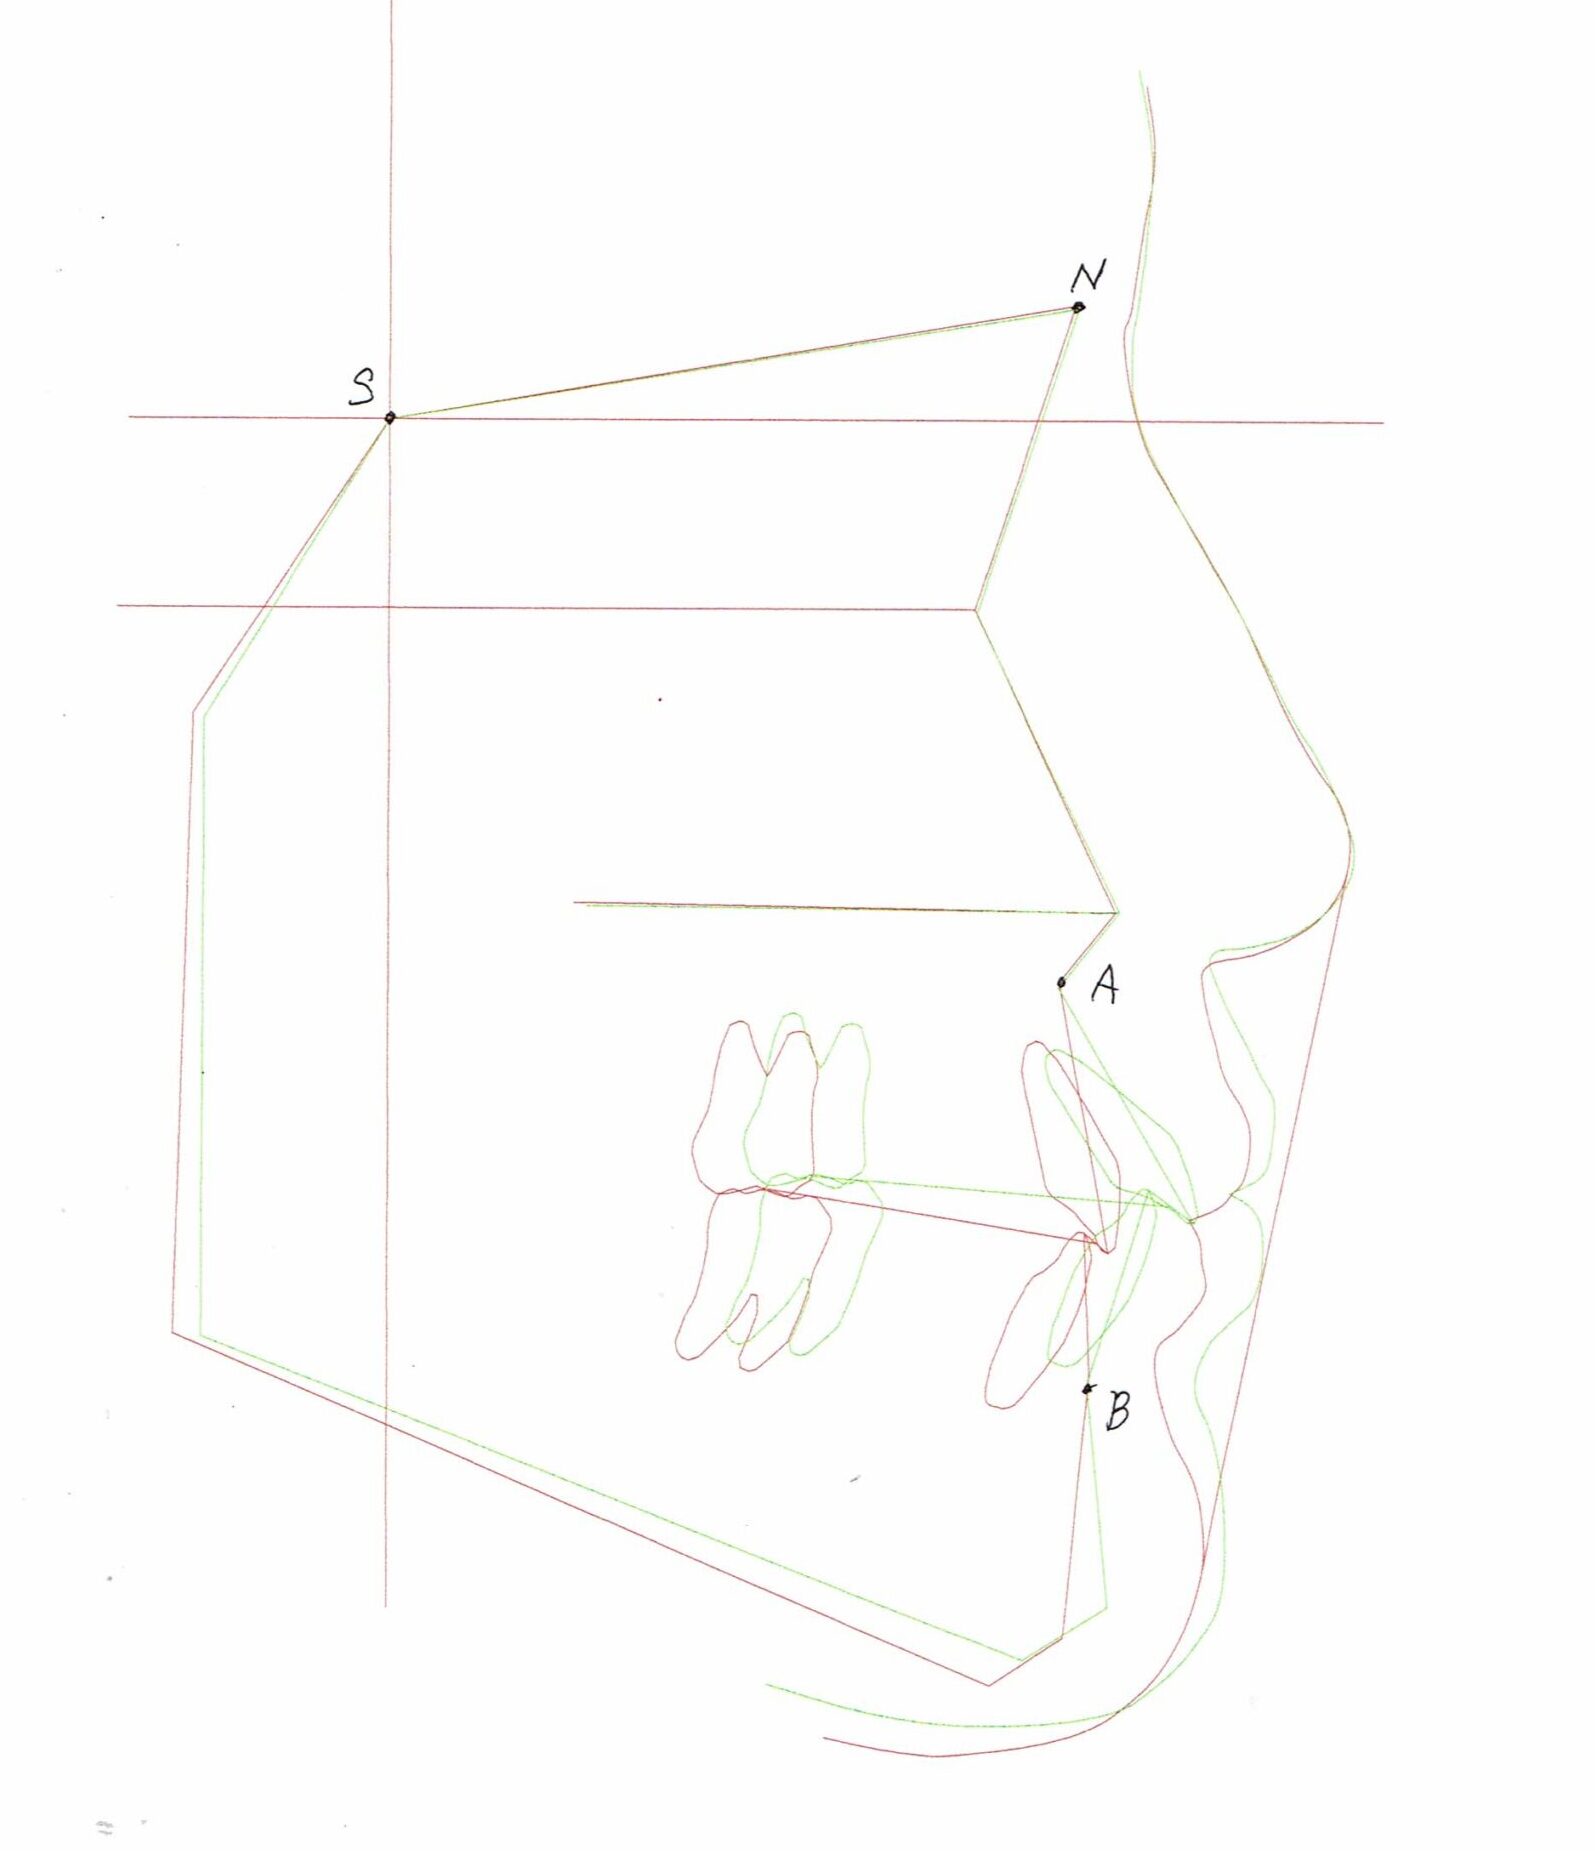

セファログラムのトレースの重ね合わせ(緑:治療前、赤:治療終了時)

治療前後の解説

| 治療前 | でこぼこしている歯による歯磨きのやりにくさや、奥歯がしっかり咬んでいない鋏状咬合(すれ違い咬合)。 出っ歯による口の閉じにくさ(口唇閉鎖不全)と、正面から見た時のオトガイ部にできる梅干し様のシワやイーラインから飛び出た口元(口ゴボ)。 機能面も審美面も気にしていた患者さんです。 治療中もなるべく装置を目立たせたくないため、ハーフリンガルでの治療となりました。 |

| 治療後 | 上下の歯がお互いにはまり込み、全体的に緊密な咬み合わせになっています。 出っ歯が治り、口元の突出感が改善されて綺麗なEラインを獲得しました。 すれ違い咬合や叢生(歯のでこぼこ)も治って歯磨きがしやすく、嚙みやすい状態になっています。 |